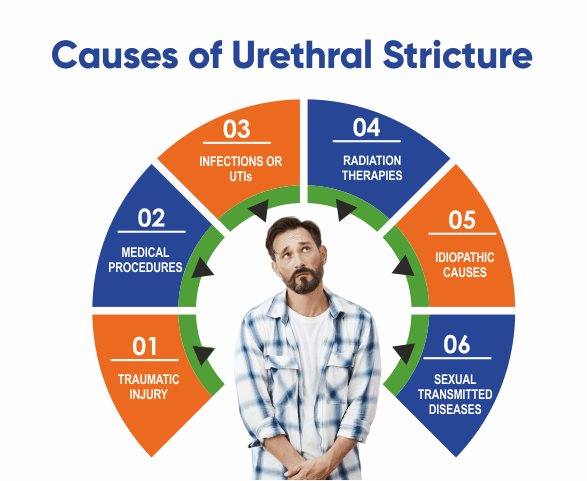

Causes of Urethral Stricture

Urethral stricture occurs when scar tissue or inflammation causes a narrowing of the urethra, restricting urine flow. The main causes include:

Previous urethral injury – Trauma from accidents, pelvic fractures, or medical procedures.

Urinary catheterization – Long-term or repeated catheter use can cause scarring.

Infections (UTIs & STIs) – Chronic urinary infections like gonorrhea or chlamydia.

Surgical complications – After prostate, bladder, or urethral surgeries.

Radiation therapy – Used for pelvic cancers, which can cause urethral damage.

Congenital defects – Some people are born with a narrowed urethra.